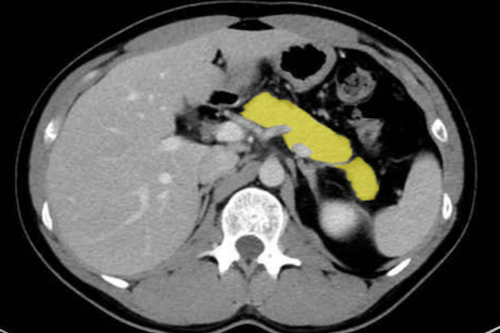

복부CT로 알 수 있는 질병

복부CT로 알 수 있는 질병들로는 간, 담낭, 췌장, 신장, 비장, 위장관, 복부 혈관까지 폭넓게 관찰할 수 있습니다. 특히 소화기 종양 진단이나 응급 복통 원인 파악에 중요한 역할을 합니다.

2. 담낭 및 췌장 질환

- 담석증: 담낭 내 결석을 쉽게 확인 가능. 초음파보다 정확도가 높습니다.

- 췌장암: 조기 발견이 어렵지만 CT에서 종괴, 췌관 확장 소견으로 추정 가능.

- 급성·만성 췌장염: 췌장의 염증, 괴사, 석회화 여부를 확인 가능.